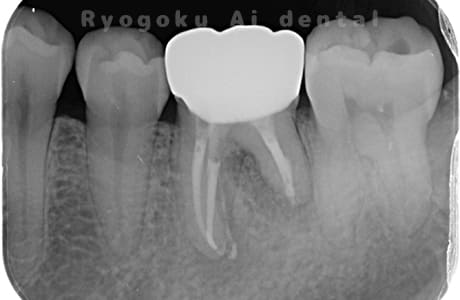

Case02

- 原因

- 慢性根尖性歯周炎

-

- 治療期間

- 3ヶ月

- 治療内容

- マイクロエンド

- 治療費用

- 121,000円

噛むと痛みが出る、とのことで来院した患者様です。他院での根管治療を終えてましたが、根尖病変を認めるため、マイクロエンドを行いました。